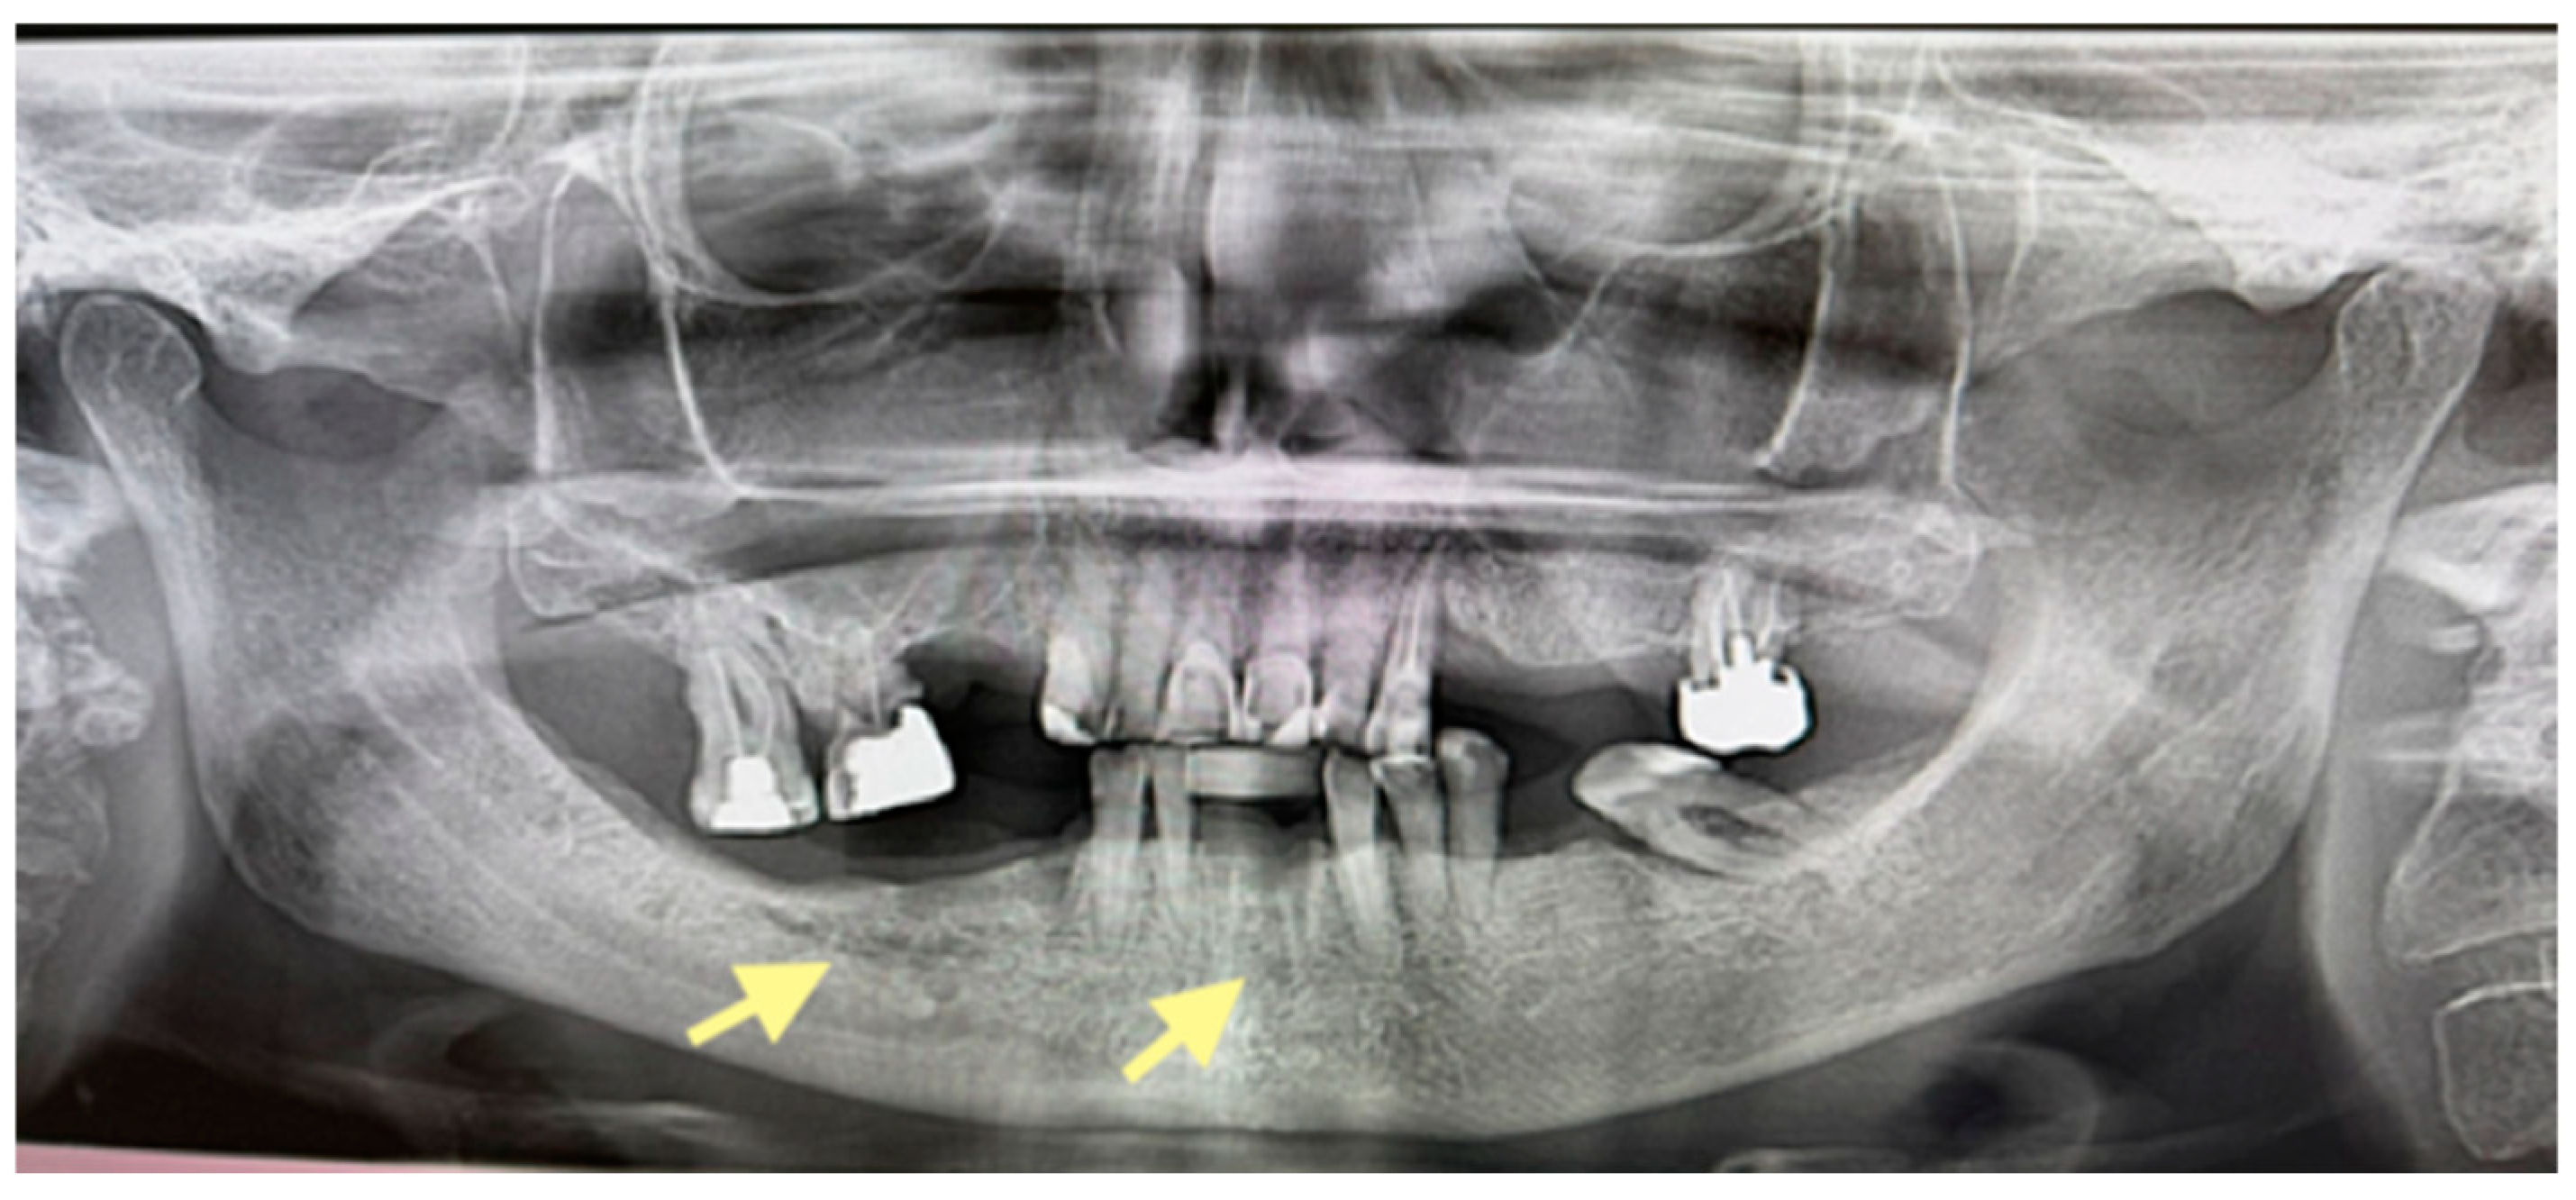

Figure 4.

OPG (orthopantomogram) before surgery (12 January 2024). In the fourth quadrant, we do not see any changes, which are typical in the initial stages of osteonecrosis.

The second patient was an 82-year-old female with osteonecrosis of the mandible in the fourth quadrant, which developed after the removal of tooth 46 on November 2023 (see Figure 4). The patient had second-stage osteonecrosis of the jaw. Initially, the patient underwent a revision of the socket of the extracted tooth and was prescribed antibacterial therapy. Despite this treatment, the patient continued to complain of a non-healing wound on the lower jaw in the area of the molars with periodic purulent discharge. In addition, these complaints were supplemented by a complaint of an intraoral fistula on the lower jaw in the area of the frontal teeth. Therefore, in May 2024, the patient underwent surgery (sequestrectomy and application of A-PRF). After the operation, the patient’s condition improved, purulent discharge from the wound stopped, the pain ceased, and the postoperative wound closed completely (see Figure 4). However, after a month, dehiscence of the wound was noted. Therefore, it was decided to repeat the operation, performed on 4 April 2025, and, in addition, to expand the scope of the surgical procedure, the sequestrectomy of the lower jaw was performed not only in the region of dd45-46 but also in the central area, simultaneously applying A-PRF. As a result of the treatment, the surgical wound on the lower jaw in the area of the molars on the right healed completely, but in the area of the incisors, it closed partially (see Figure 5 and Figure 6).